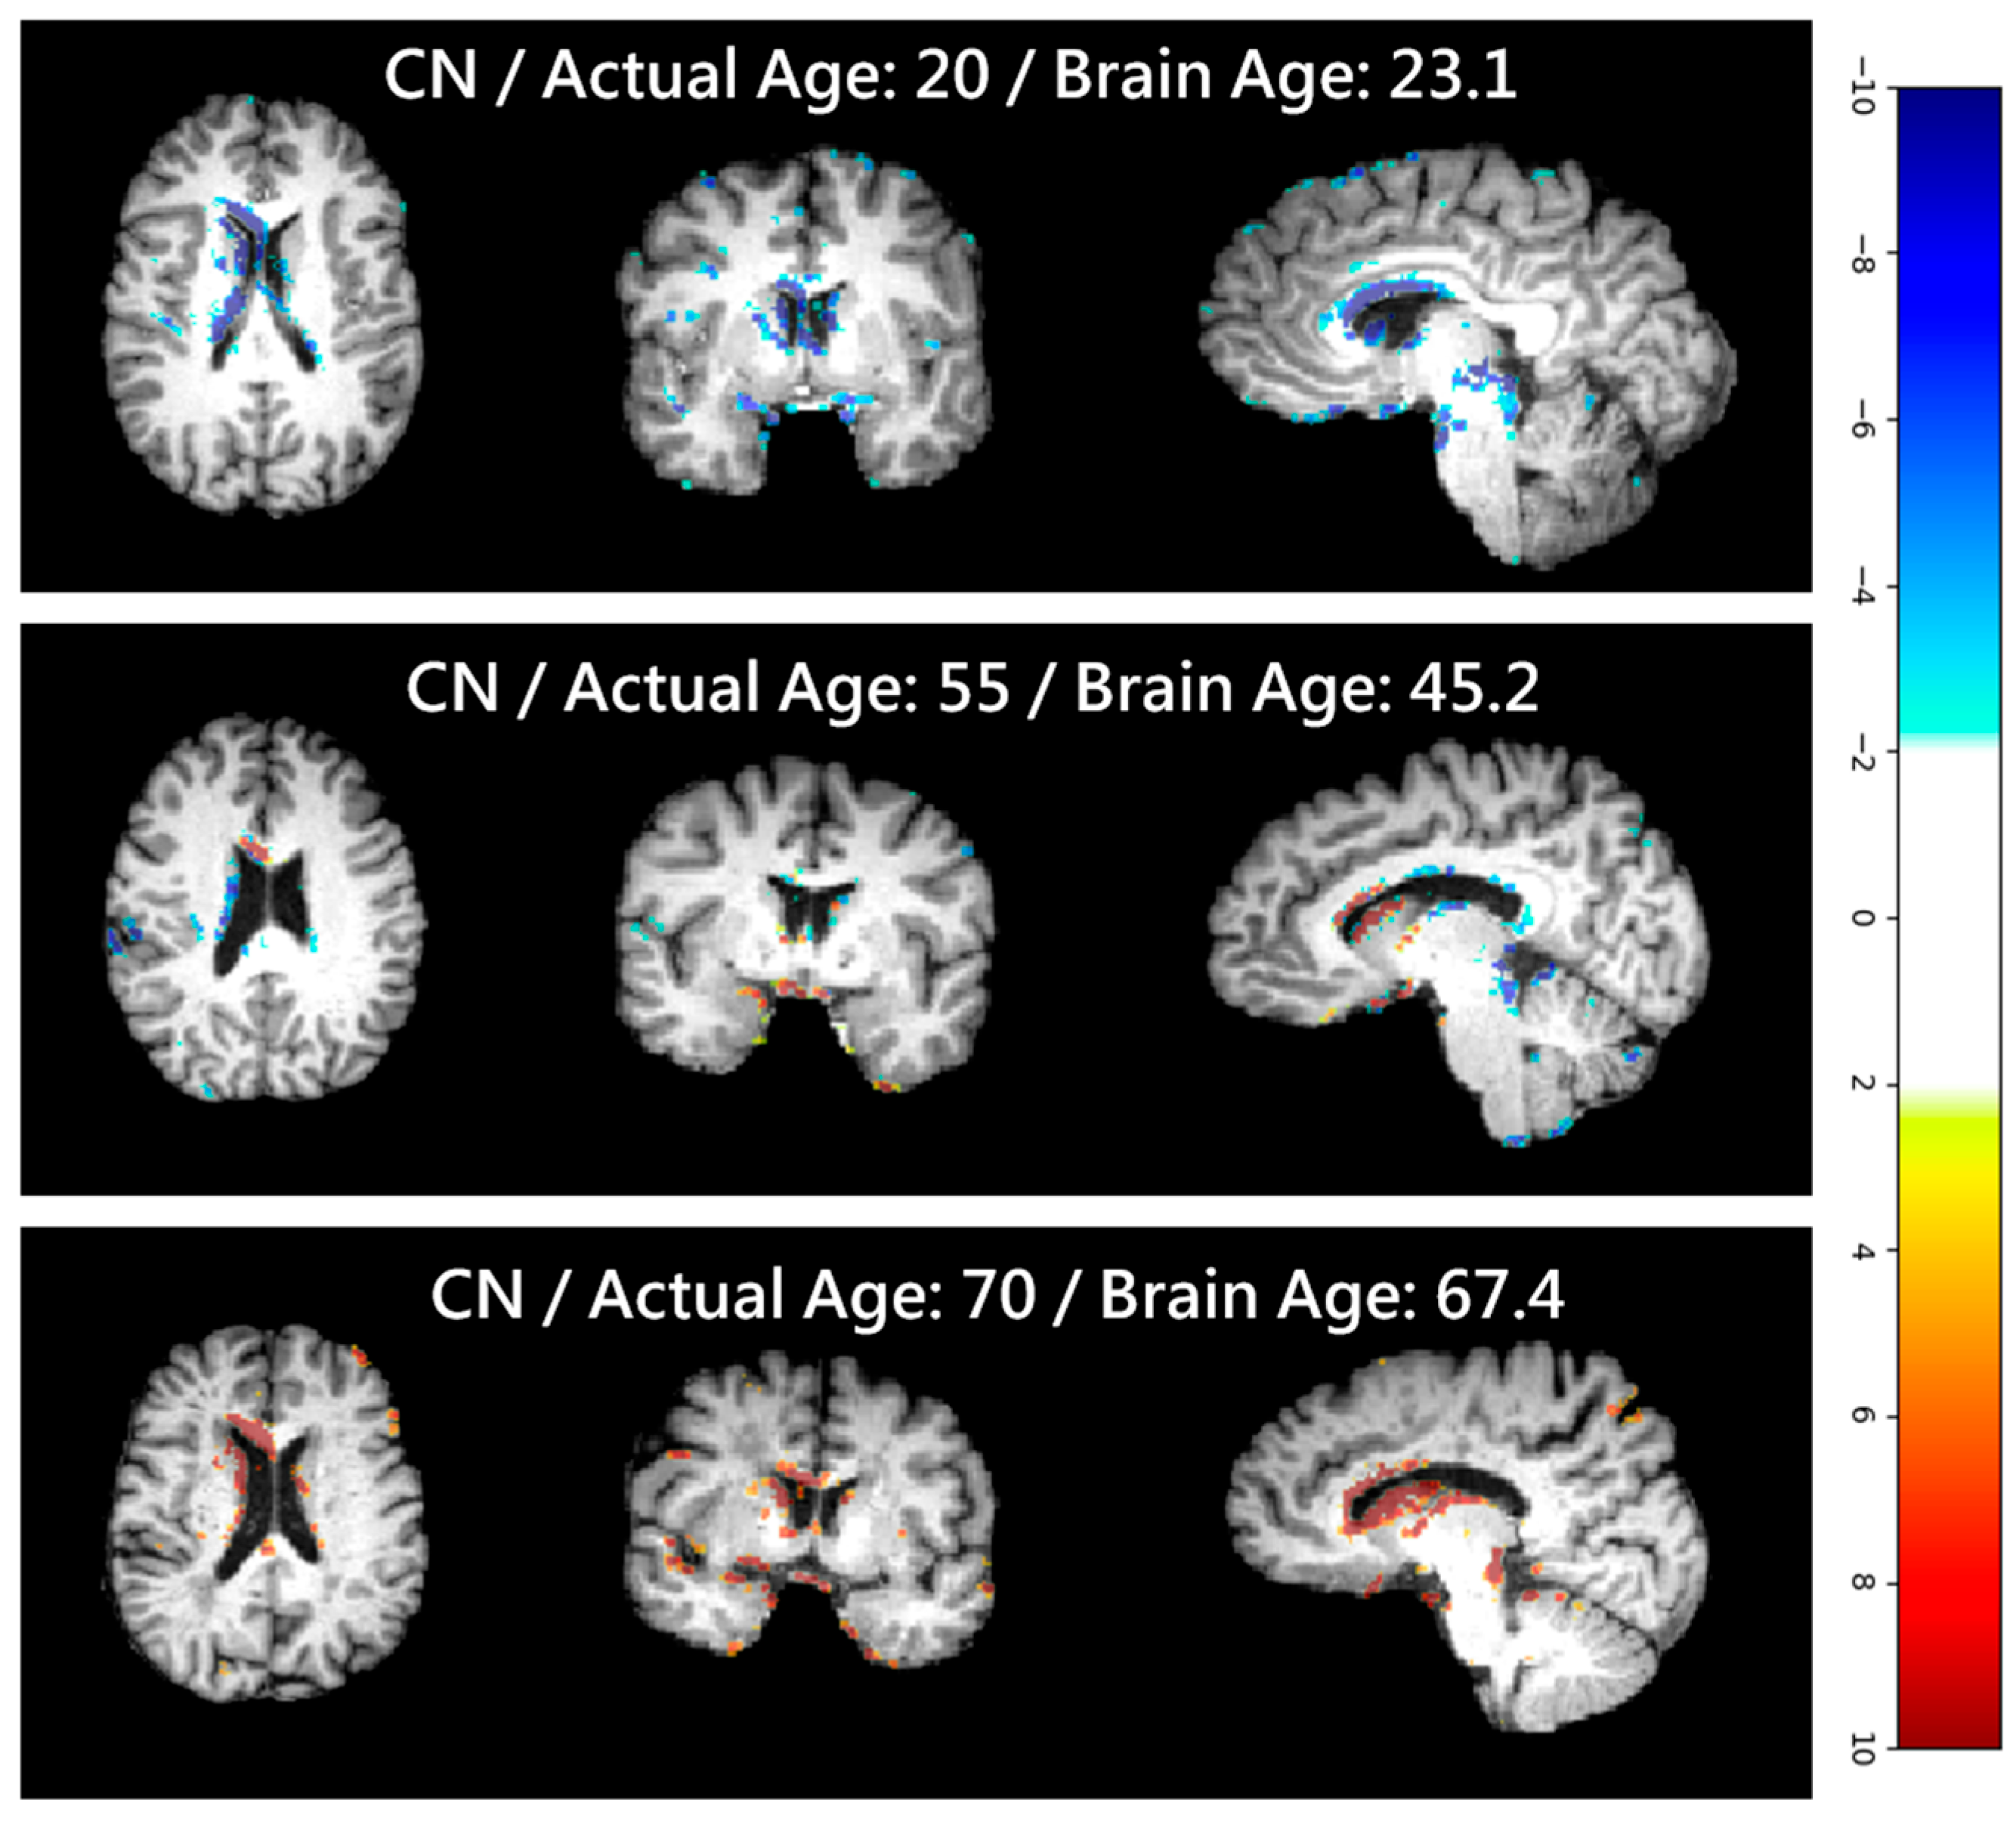

4.6. Softmax-Derived Brain Age Mapping Analysis